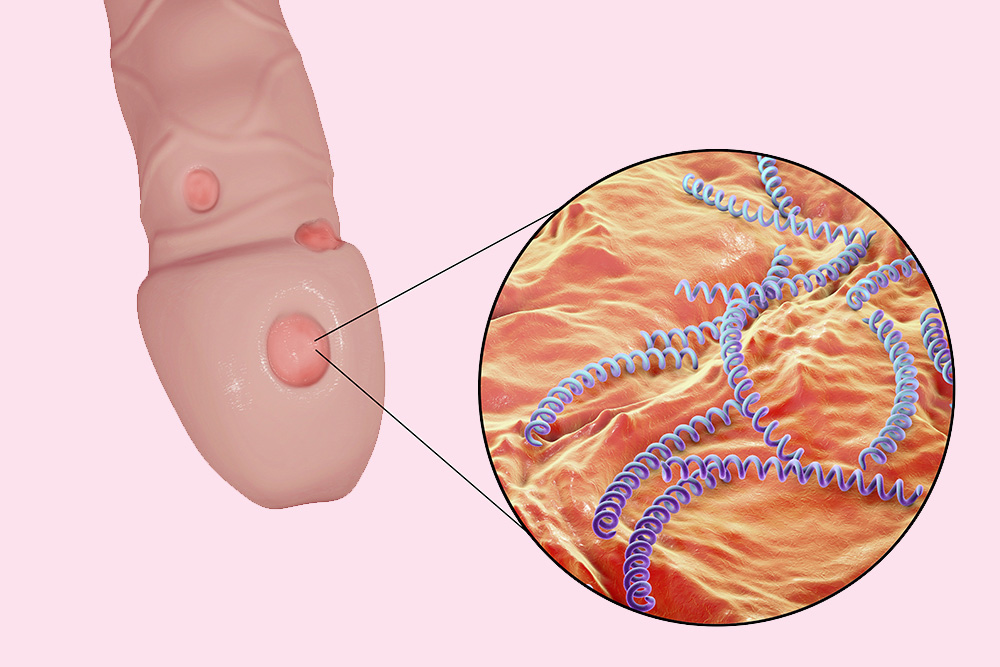

会陰部 男性-男性 感染後3~12日で会陰部や直腸粘膜に5~8mmのびらん・丘疹が発生します。 やがて潰瘍になりますが、痛みがなく数日で治ってしまうので、本人が気づかないことも多いです。 その後1~2週間で、鼠径リンパ節や大腿部リンパ節が腫れます。前立腺の病気には慢性前立腺炎、急性前立腺炎、前立腺肥大症、前立腺癌などがあります。 慢性前立腺炎 あまり知られていない病名ですが、罹患されている男性は多く、すでに治療 中でなかなか良くならず悩んでおられる方も多いと思われます。 命に関 わる病態ではありませんが、ご本人に

会陰 ( えいん )とは、 解剖学 において、狭義では 外陰部 と 肛門 の間、広義では左右の 大腿 と 臀部 で囲まれる 骨盤 の出口全体をさす。 恥骨結合 と左右の 坐骨結節 、 尾骨 を結ぶ菱形部となる。会陰と残尿感の解消には、 一体どのような関係性があるのでしょうか。 男性は蟻の門渡りを押すことで残尿感を解消できるのか? 排尿を終えた直後なのに「まだ膀胱内に尿が残っているような気がする、 なんだかスッキリしない」という不快感を覚える 男性の陰部のかゆみの原因として考えられる疾患とは? 男性の陰部にかゆみの症状があるとき、大まかな原因としては「性感染症」「皮膚疾患」の2つの場合が考えられます。 かゆみのある性感染症としては「性器ヘルペス・尖圭コンジローマ・梅毒」などがあり、どれも性行為により感染する可能性があります。 性器ヘルペスでは、陰部に水膨れができ

男性の性器ヘルペス 新宿 泌尿器科専門サイト